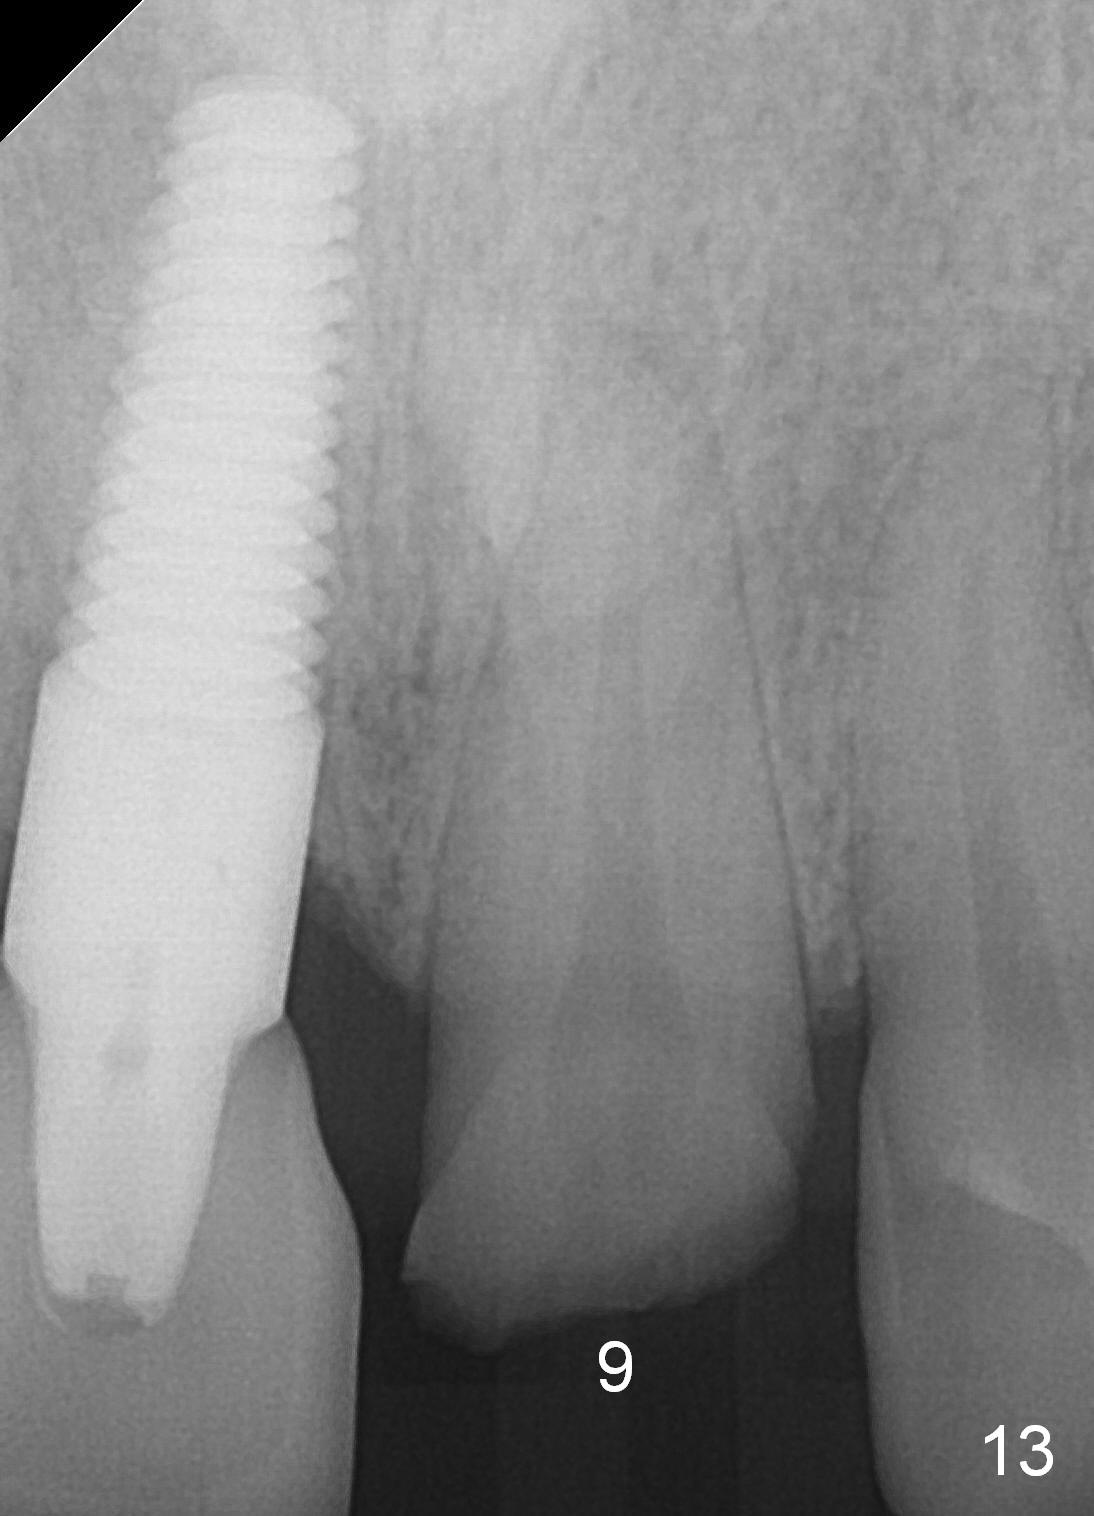

When the patient returns 3 years 10 months post cementation, the tooth #9 fractures (Fig.13,15,16), and receives root canal therapy (Fig.14). The dark gingiva could be avoided if the implant is placed more palatally and smaller in diameter (Fig.15,16).